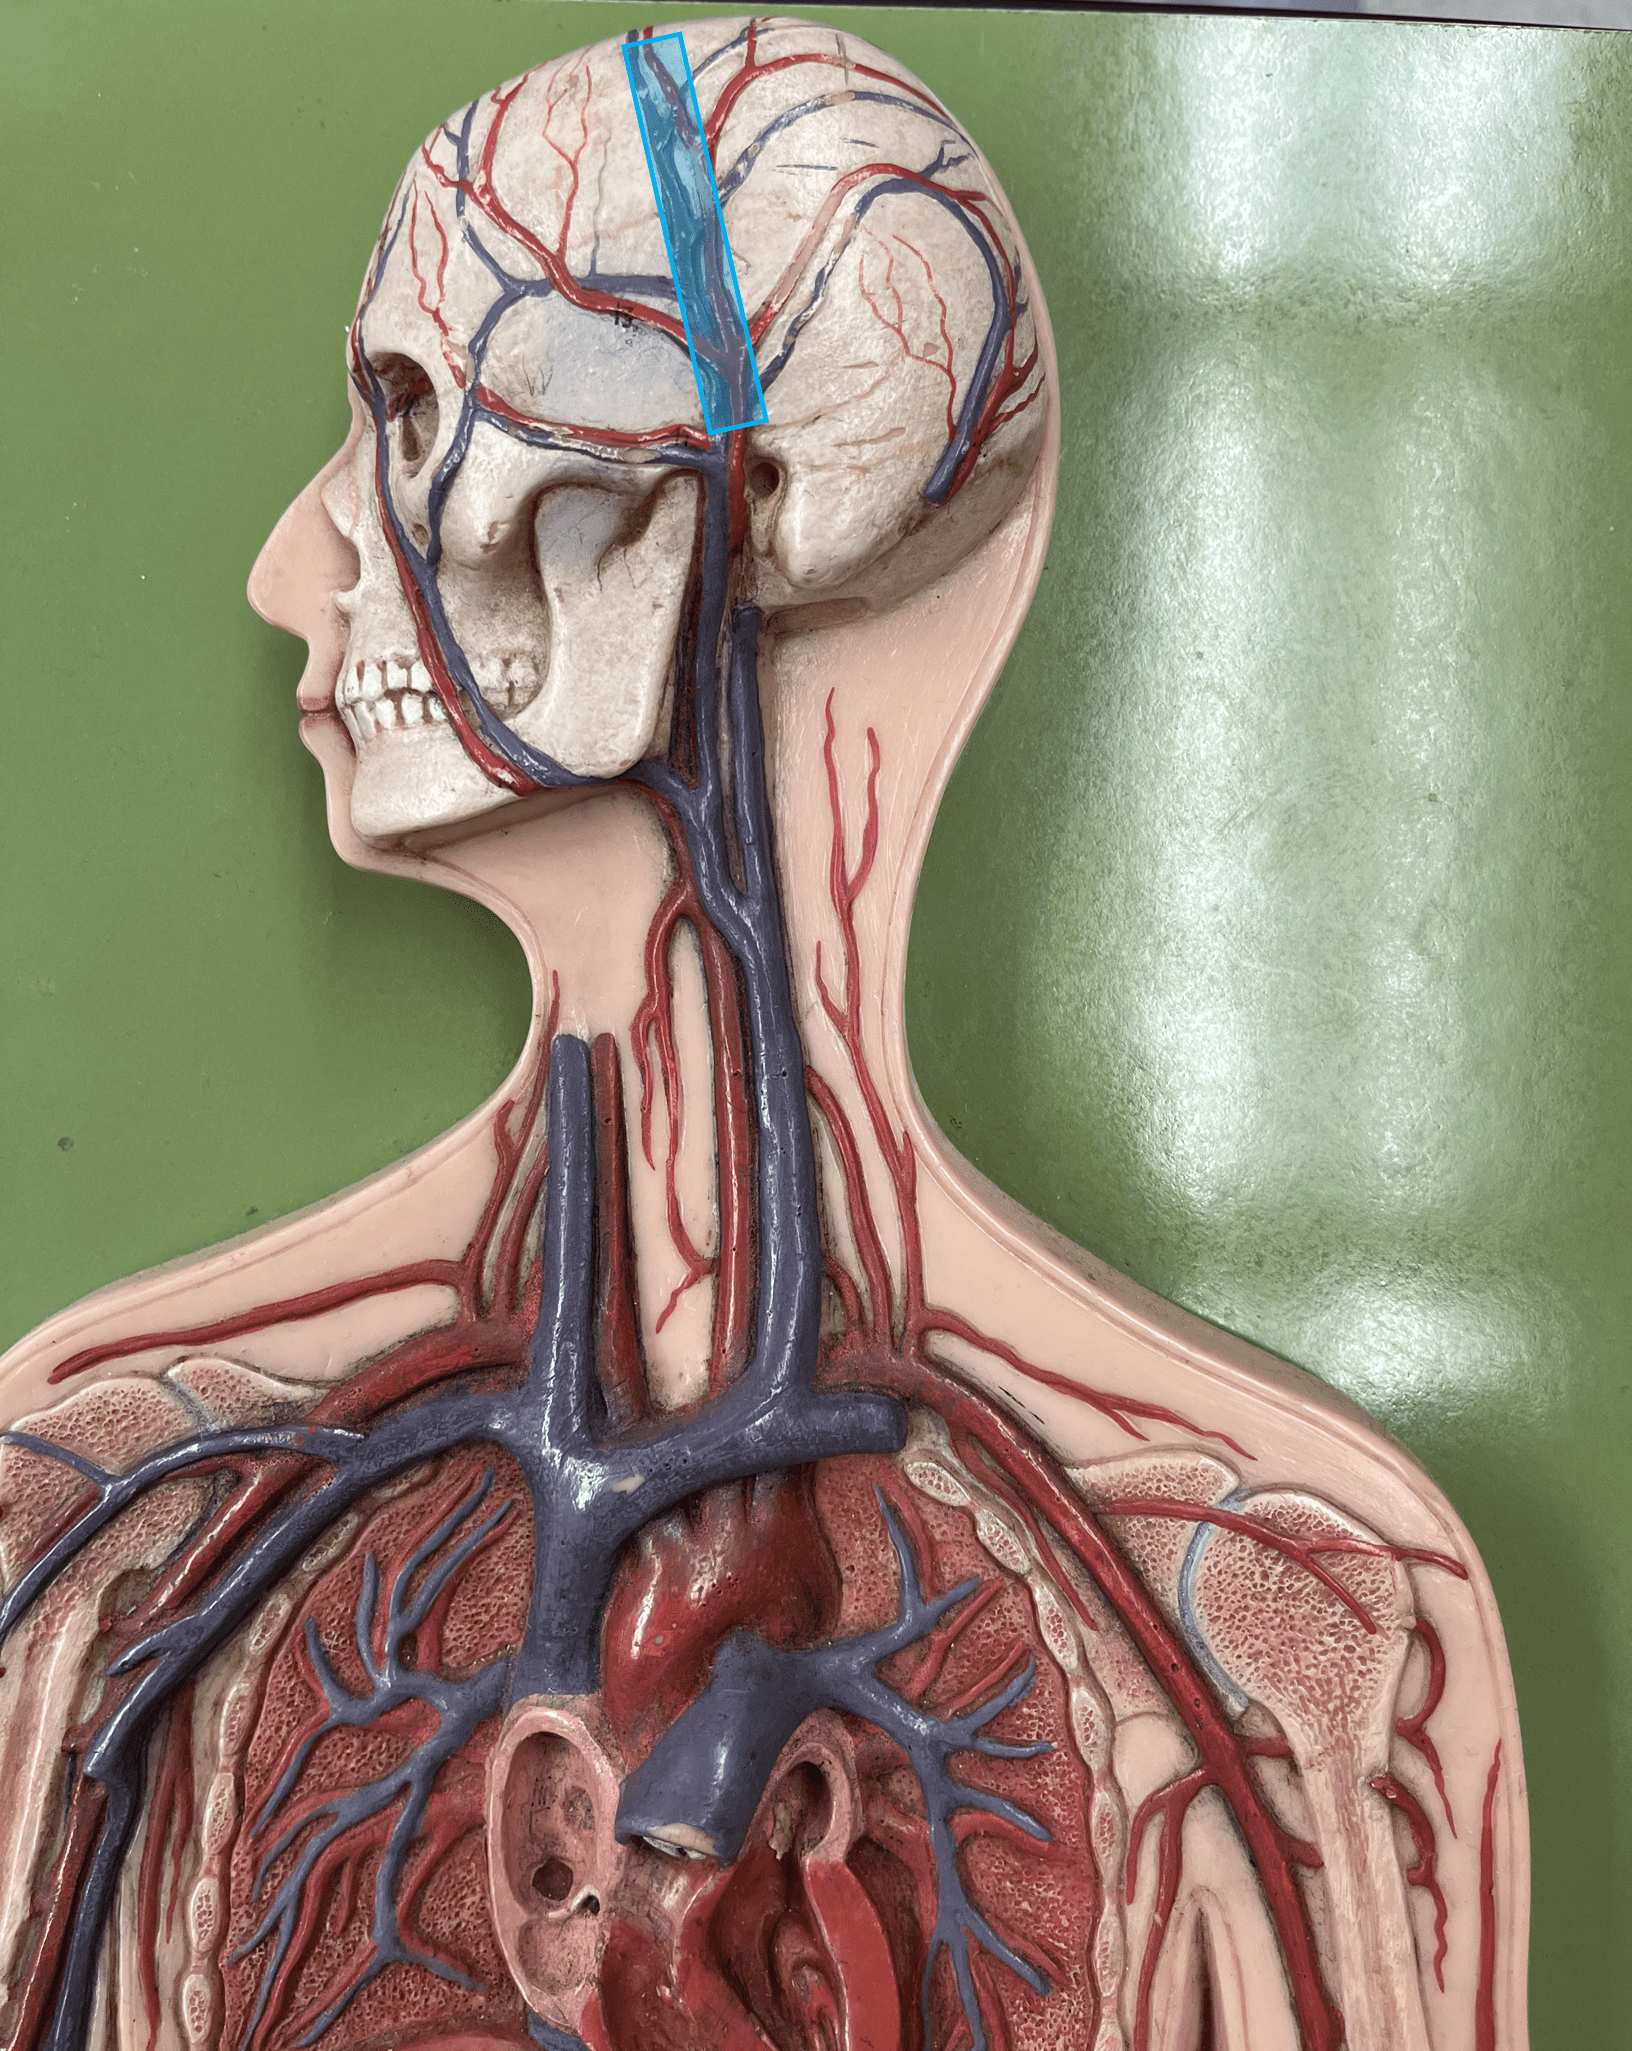

superior sagittal sinus

• A vein of the cerebral circulation.

• Drains the superficial brain.

• Empties into the internal jugular vein.

• Drains the superficial brain.

• Empties into the internal jugular vein.

34

New cards

inferior sagittal sinus

• A vein of the cerebral circulation.

• Drains the deep brain.

• Empties into the internal jugular vein.

• Drains the deep brain.

• Empties into the internal jugular vein.

35